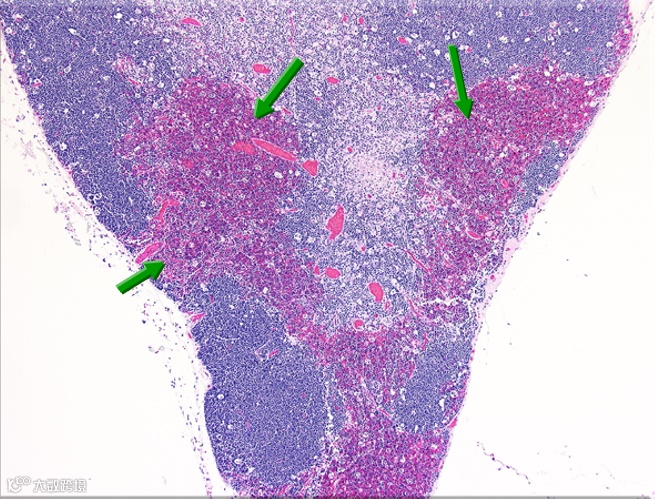

应激可导致淋巴组织内淋巴细胞溶解或解体,如下图所示。

大鼠胸腺 皮质-髓质层交界处急性出血

大鼠胸腺-坏死的淋巴细胞碎片

慢性应激变化可导致淋巴细胞耗尽和淋巴组织萎缩,应正确辨别细胞正常、细胞退化、组织萎缩的差异。